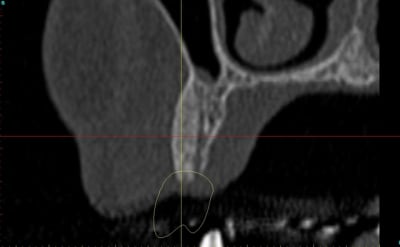

dentiste57 écrivait:

--------------------

> et là ?

> greffe selon ta méthode ?

Cross section dhvkc8 - Eugenol

3d dt3qom - Eugenol

Overview uqcp6u - Eugenol

S2y2o1v7q53ws4r5wy6ou8czrpom - Eugenol

pxav

01/05/2011 à 12h55

> dentiste57 écrivait:

> --------------------

> > et là ?

> > greffe selon ta méthode ?

expansion, c'est plus cool!